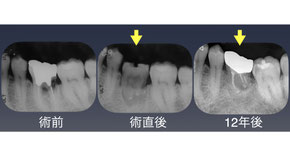

■患者さんの訴え

「右下の歯が取れた」

■治療内容

右下第二大臼歯を抜歯し右下智歯(親知らず)を移植した。